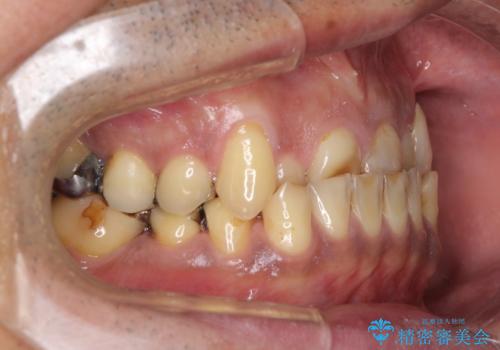

骨格的な反対咬合により上顎前歯の先端が顕著にすり減っている状態でした。

奥歯の欠損が散見されており、銀歯の装着されている歯も多いため、ワイヤー矯正にて歯列を調整し、その後オールセラミッククラウンにて補綴治療を行うこととしました。

反対咬合改善には奥歯の咬み合わせをしっかりと改善させることが必要となりますが、奥歯に欠損が多いため、矯正治療が難航することが予想されます。